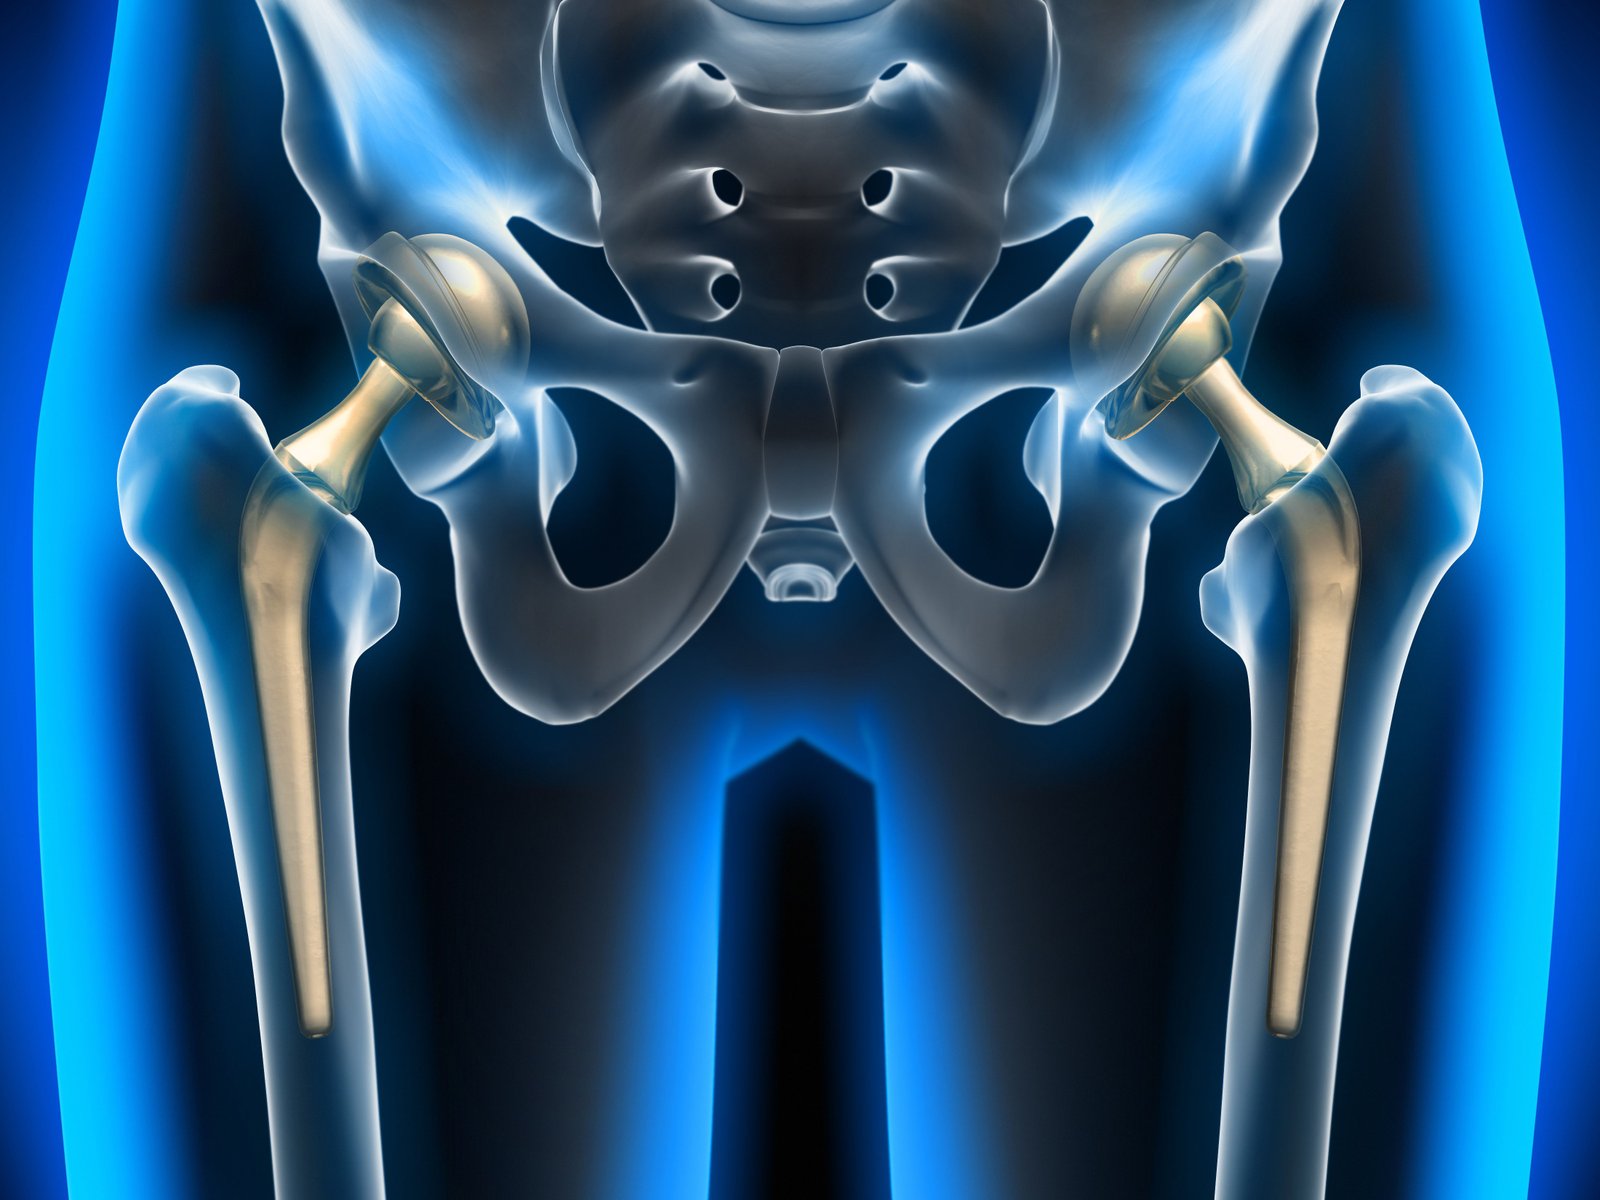

In this surgery, our surgeon surgically removes a damaged bone and cartilage caused by arthritis and replaces it with a metal or plastic prosthesis as an artificial joint. This hip replacement operation can treat patients with hip pain and make walking simpler for them.

Hip replacement can also be performed using a minimally invasive approach with a small incision. Our orthopaedic surgeon will use either general anaesthetic or a spinal block to numb the lower part of the body during the surgery. In India, we have approximately 20 years of experience in Hip Replacement Surgery and Revision Hip Replacement Surgery.

The surgery procedures vary from patient to patient based on their problem. In this surgery, our surgeon surgically removes a damaged bone and cartilage caused by arthritis and replaces it with a metal or plastic prosthesis as an artificial joint. This hip replacement operation can treat patients with hip pain and make walking simpler for them.